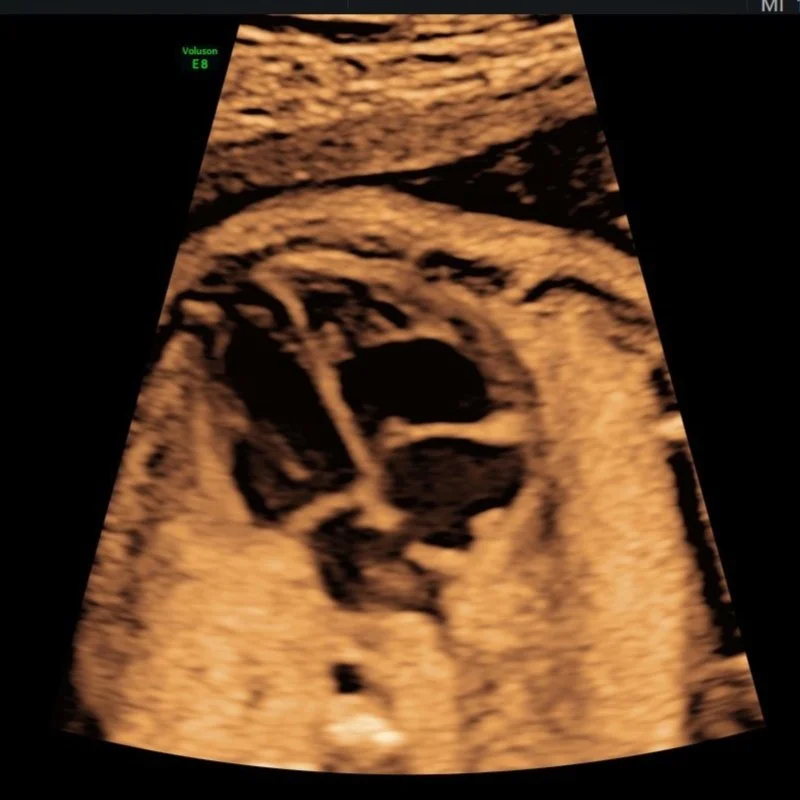

A routine Ultrasound examination is offered to most women at 19-22 weeks. This scan is often referred to as a Morphology or 20 week ultrasound.

- Perform a detailed assessment of the developmental anatomy of the fetus’ head, brain, face, lips, palate, heart, diaphragm, lungs, kidneys, abdominal wall, bladder, spine, skin line, arms, hands, legs and feet.

Our Morphology Scans take up to 50 minutes and include:

- 2 x 3D thermal printed hard copy images

- All pictures taken on the day straight to your mobile phone